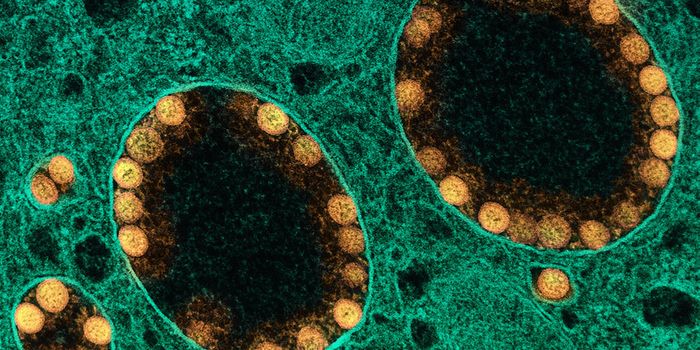

JUL 18, 2024ImmunologyCoronavirus disease (COVID-19) caused by the SARS-CoV-2 virus resulted in the fatality of millions worldwide. This sever ...